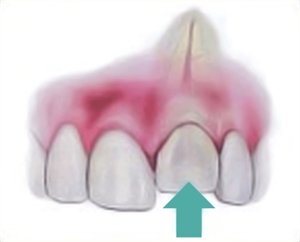

Dental intrusion - facial and occlusal view. How the intruded tooth looks on a dental x-ray

Intrusion usually means to enter a territory that you are not supposed to be in. In dentistry, intrusion refers to a fractured condition of the tooth, where the tooth breaks through the socket it is supposed to be in and goes on to travel in an inward direction.

The socket we are talking about is one of the four components that keeps the tooth stable in its position. When an individual is involved in an accident, the traumatic blow might be in a direction that would force the tooth to penetrate deeper into the socket, thereby adversely breaking it. The most common teeth that are involved in such traumatic conditions are the upper front teeth. Since these teeth intrude beyond their original positions, deep into the bony area, the type of fracture is called dental intrusion.